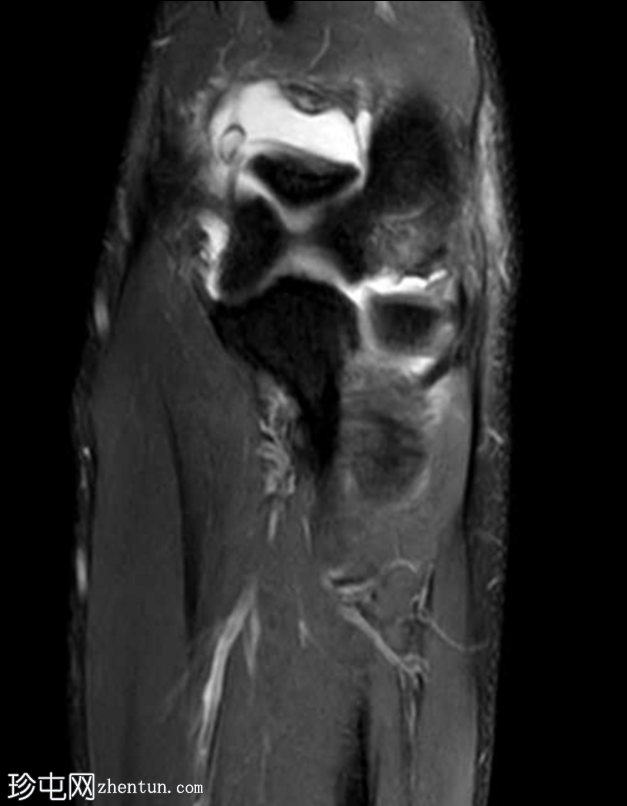

矢状位

T2加权像

尺侧副韧带显示高度撕裂,表现为模糊的异常形态,并伴有高PD信号强度。

内侧副韧带前束近端附着点显示高PD和STIR信号以及纤维断裂,符合部分撕裂的特征。

桡骨近端周围存在广泛的软组织水肿和液体信号,提示环状韧带损伤。

旋后肌显示明显的水肿,且肱二头肌腱附着处信号异常。

另可见大量关节积液。